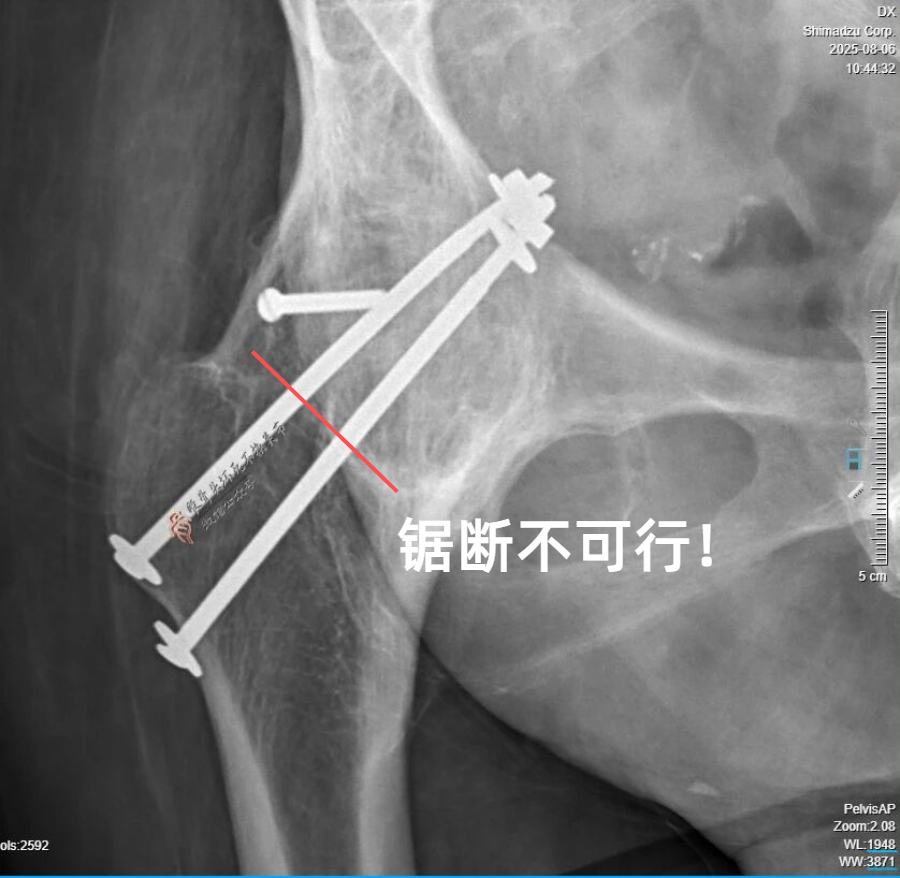

髋关节骨性融合20余年,进行关节置换必须完全取出内固定,否则髋臼假体的安装就无法实现;残存内固定轻则影响假体安装,重则造成血管神经损伤,甚至危及生命。

之前采用的是金属螺栓固定,且螺母在髋臼内壁,所以不能存留任何内固定,即便取不出来,臼底就是开窗也要拿出来,但那样做无疑创伤非常大、危险也随之而来。

当然,如果内固定不能完整取出的话,也可以摆锯锯断,化整为零,但问题是:

如果是不锈钢材质,如果没有氮化铬涂层、紫蓝PVD涂层的特种锯片,根本无法锯断——医用摆锯和钢钉硬度接近,无法相克——手术将被迫中止。

而后来证实,20多年前还真是一个主打不锈钢的年代,的确是全套不锈钢——想想都后怕!